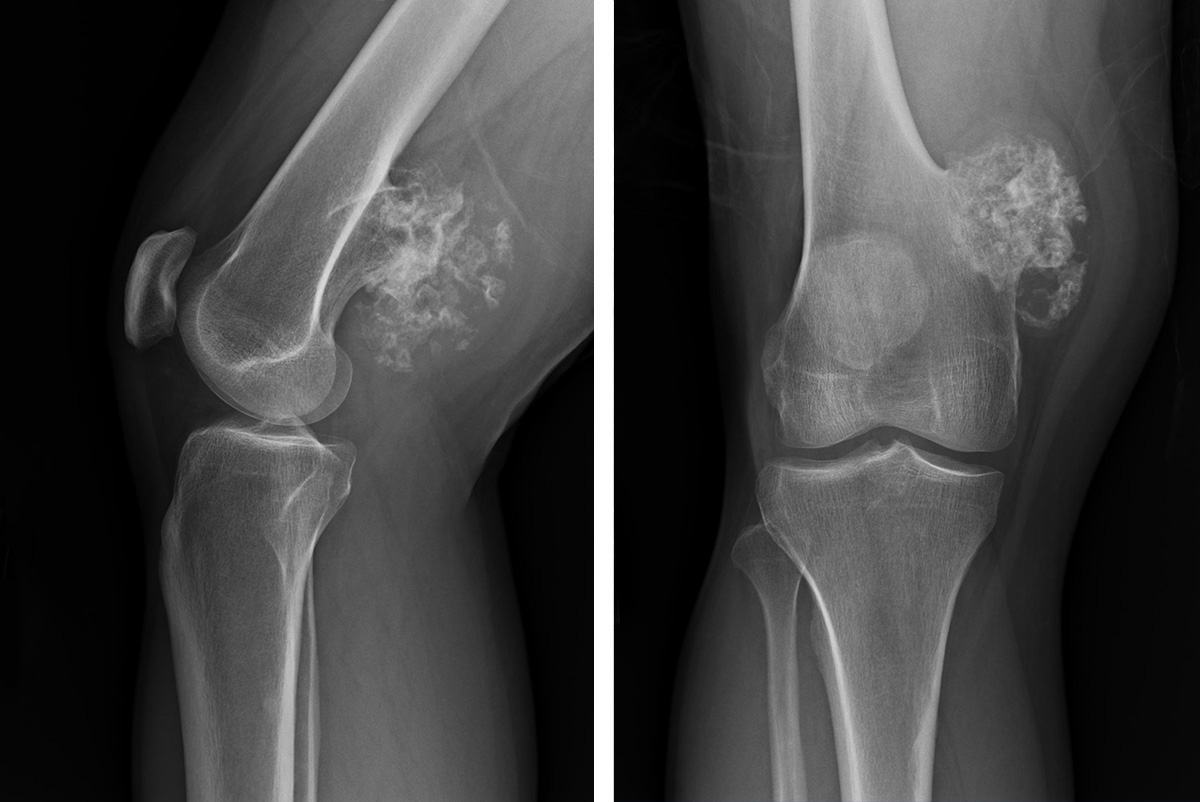

Bone Tumors

Bone tumors develop when cells within a bone divide uncontrollably, forming a lump or mass of abnormal tissue. Most bone tumors are benign (not cancerous). Benign tumors are usually not life-threatening and, in most cases, will not spread to other parts of the body. Depending upon the type of tumor, treatment options are wide-ranging—from simple observation to surgery to remove the tumor.

Some bone tumors are malignant (cancerous). Malignant bone tumors can metastasize—or cause cancer cells to spread throughout the body. In almost all cases, treatment for malignant tumors involves a combination of chemotherapy, radiation, and surgery.